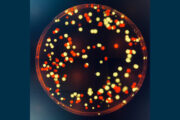

Gleich und doch verschieden: wie sich nahverwandte Bakterien unterscheiden

Einzelne Pseudomonas-aeruginosa-Bakterien unterscheiden sich in ihrem Typ-VI-Sekretionssystem: Die Studienergebnisse geben Einblick in die Evolution nahverwandter Bakterien und könnten neue Ansätze Diagnose und Behandlung von Infektionen liefern.